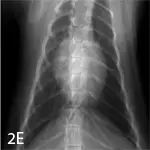

Right lateral (A), left lateral (B), and ventrodorsal (C) thoracic radiographs from a 7-year-old mixed breed neutered male dog. Right lateral (D) and ventrodorsal (E) images from a 4-year-old neutered male domestic shorthair cat. In both cases, the radiographs were deemed normal.